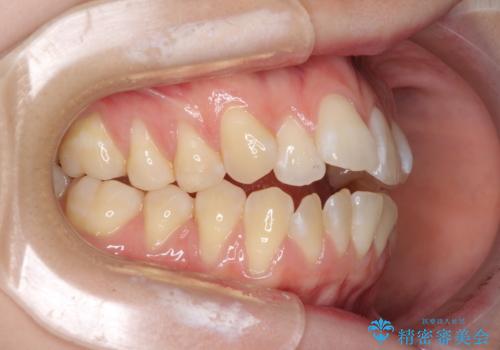

気になるデコボコとオープンバイト インビザラインでの矯正治療

- 前歯のデコボコと上下が開いていることを気にして来院された患者様です。

いわゆるオープンバイトは、インビザラインによる治療が適しているため、インビザラインにて治療を行うこととしました。

オープンバイトは容易に後戻りを起こすため、少しでも後戻りリスクを軽減するために舌癖改善のトレーニングをしっかりと行っていただきました。